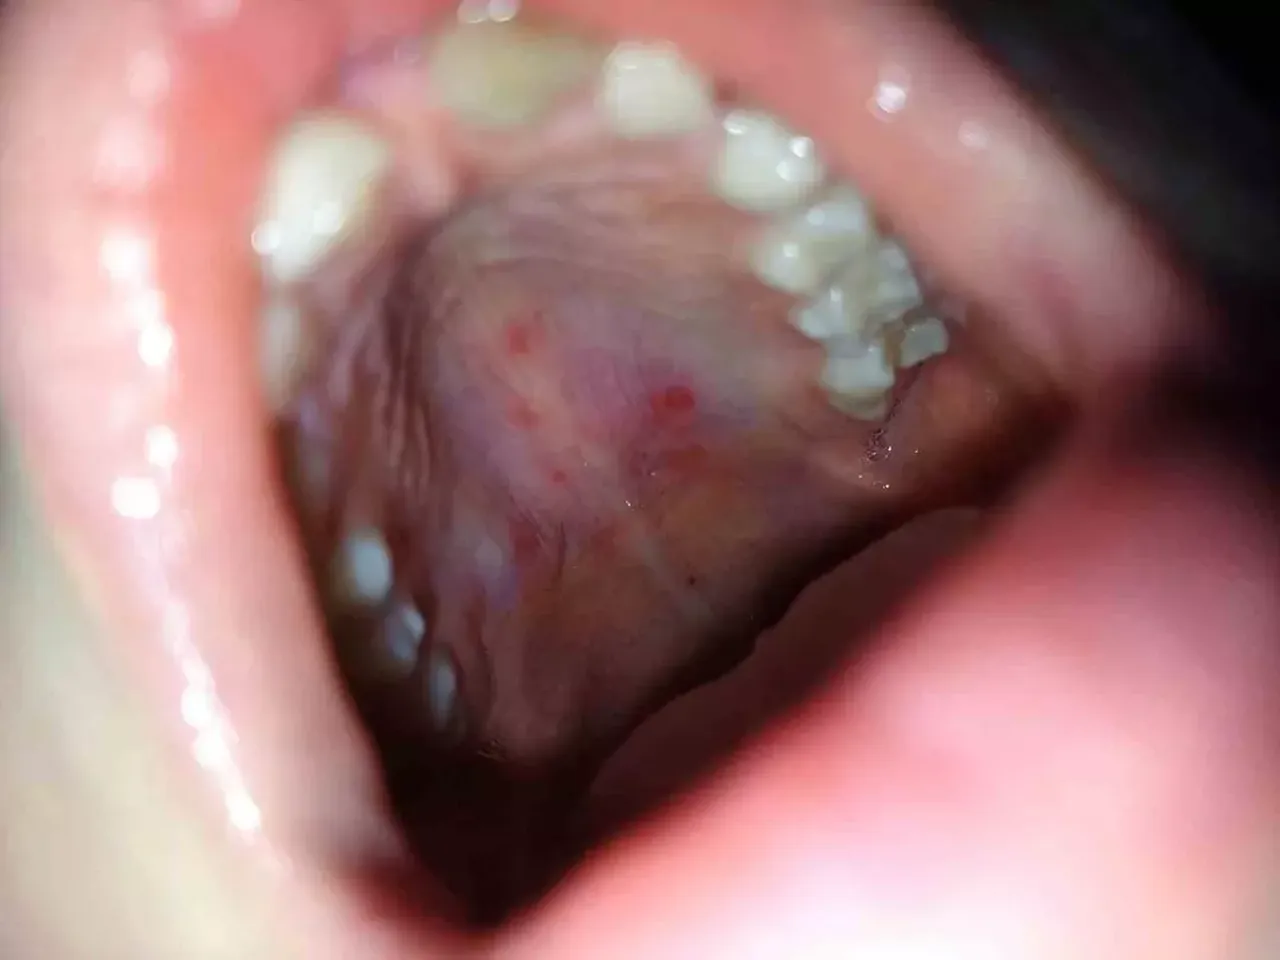

Dr. Fil’e göre el, ayak ve ağızda oluşan lezyonlarla kendini gösteren hastalık, özellikle 5 ila 7 yaş arası çocukları hedef alıyor. Hastalık; yüksek ateş, boğaz ağrısı, iştah kaybı ve ağız içinde ağrılı yaralarla ortaya çıkıyor. Coxsackievirus A16 ve enterovirüs 71 kaynaklı bu viral enfeksiyon, çocuklardan yetişkin bireylere kadar herkesi etkileyebiliyor.

Hastalığın belirtileri arasında yüksek ateş (38-40°C), ağız içi yaralar, ellerde ve ayaklarda içi sıvı dolu döküntüler, iştahsızlık ve halsizlik yer alıyor. Dr. Fil, “Özellikle ağız yaraları çocukların beslenmesini zorlaştırır. Ayrıca döküntüler ilk başta kızarıklık şeklinde başlar, zamanla kabarcıklara dönüşür” diyerek aileleri uyarıyor.